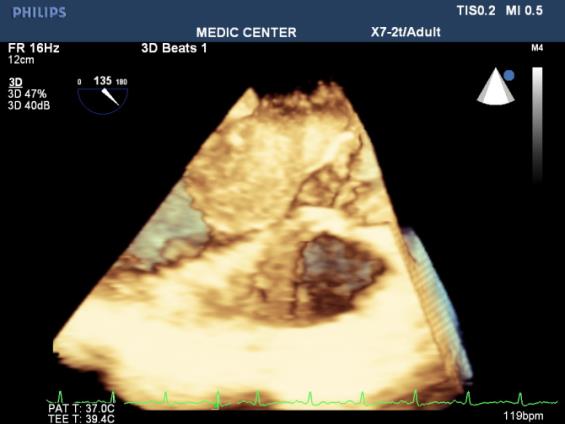

Three-dimensional (3D) TEE images can be rotated to demonstrate the defect from the RA or LA side in evaluating the secundum atrial septal defect rims. This improves understanding of their shape and relationships to surrounding intracardiac structures.

Multiple ASDs account only 4%, 3D TEE with wide sector can detect and visualize all the shunts through IAS (Figures 22-37).

Figure 23. 3DTEE Zoom mode presenting a secundum ASD (shape, size, all rims)

Figure 25. 3D image better demonstrates the shape and size of the secundum ASD

Figure 26. L-R shunting secundum ASD demonstrated with color flow imaging

Figure 32. Secundum ASD viewed from LA

Figure 33. Secundum ASD visualized on 3DTEE Zoom mode